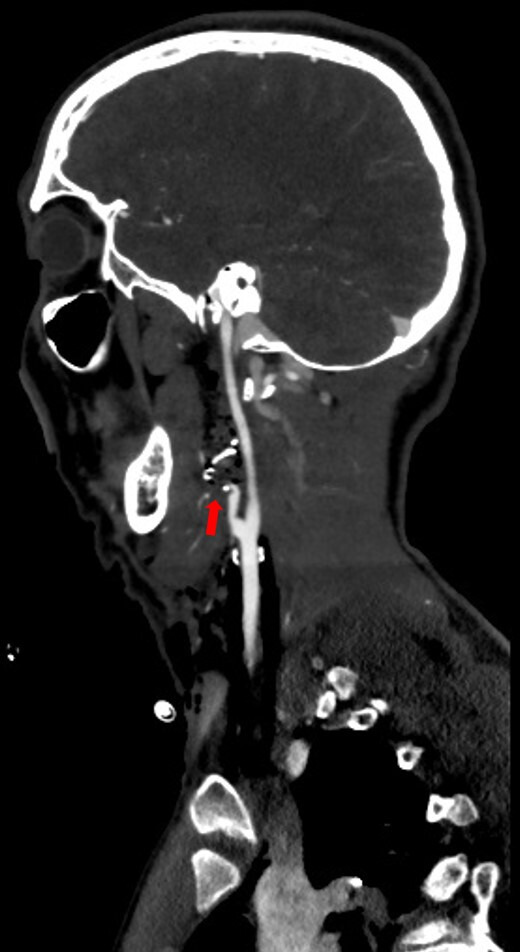

Management of penetrating neck injury to zone III in an initially unstable patient.

最初不稳定患者颈部穿透伤至III区的处理。